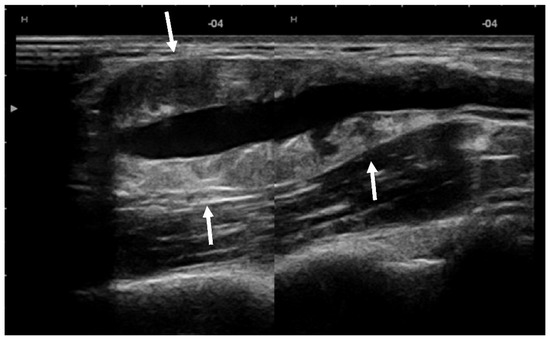

| Manole et al./2022 | US | First-line imaging tool |

| - detection and characterization | ||

| - assessment of the vessel | ||

| - follow-up | ||